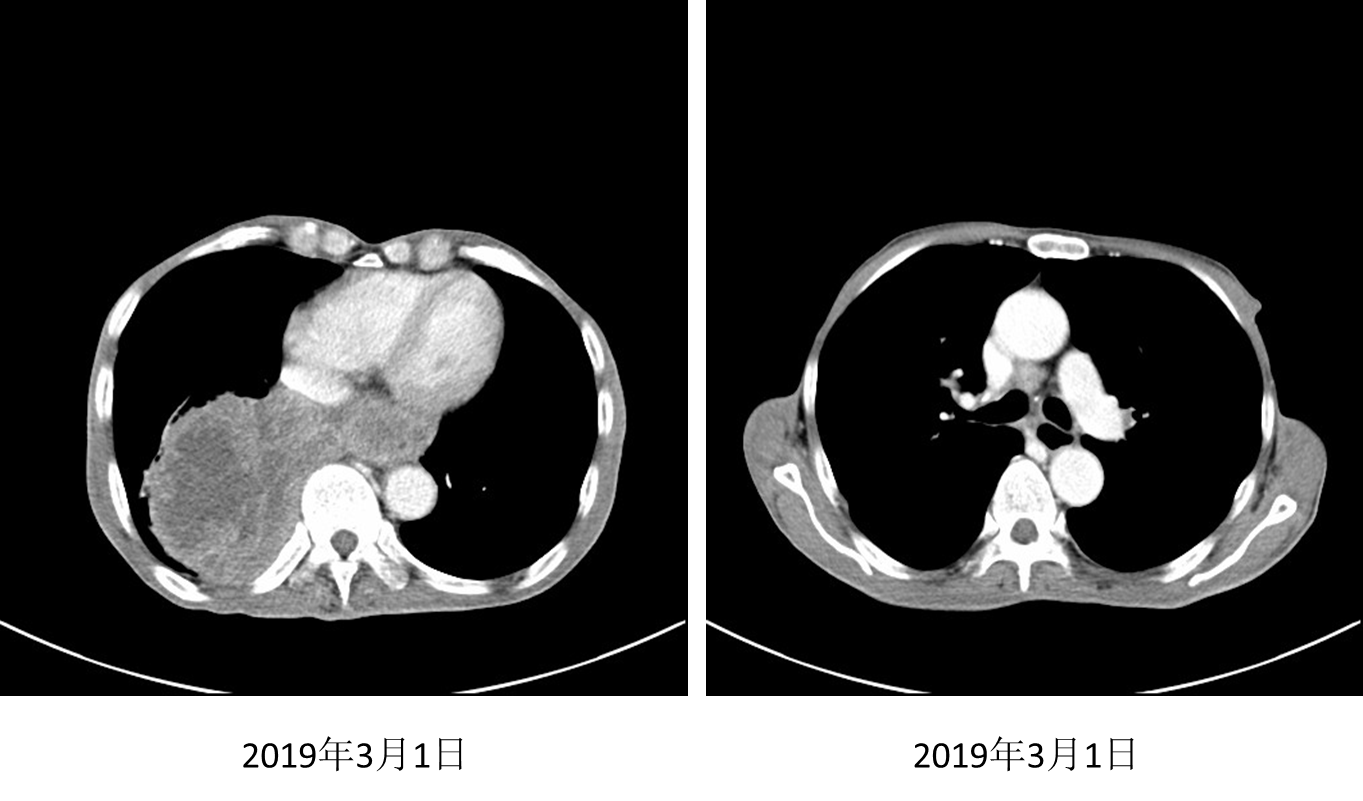

2018年12月至2月接受安罗替尼12mg/d治疗3个月;2019年3月1日复查,胸部肿块较前增大,且胸闷闭气症状加重,评价为疾病进展(PD)。

image005.png

图3. 2019年3月1日胸部CT

在沟通疗效和价格等因素后,患者自行选择信迪利单抗。2019年4月3日、4月30日、5月21日行信迪利单抗200mg D1治疗3个周期,患者症状缓解(自诉从“躺在床上”到“早上逛菜市场”)。2019年5月24日复查胸部CT示:右肺下叶软组织肿块影范围较前明显缩小,强化不均,范围约77mm *50mm。

图4. 2019年5月24日复查